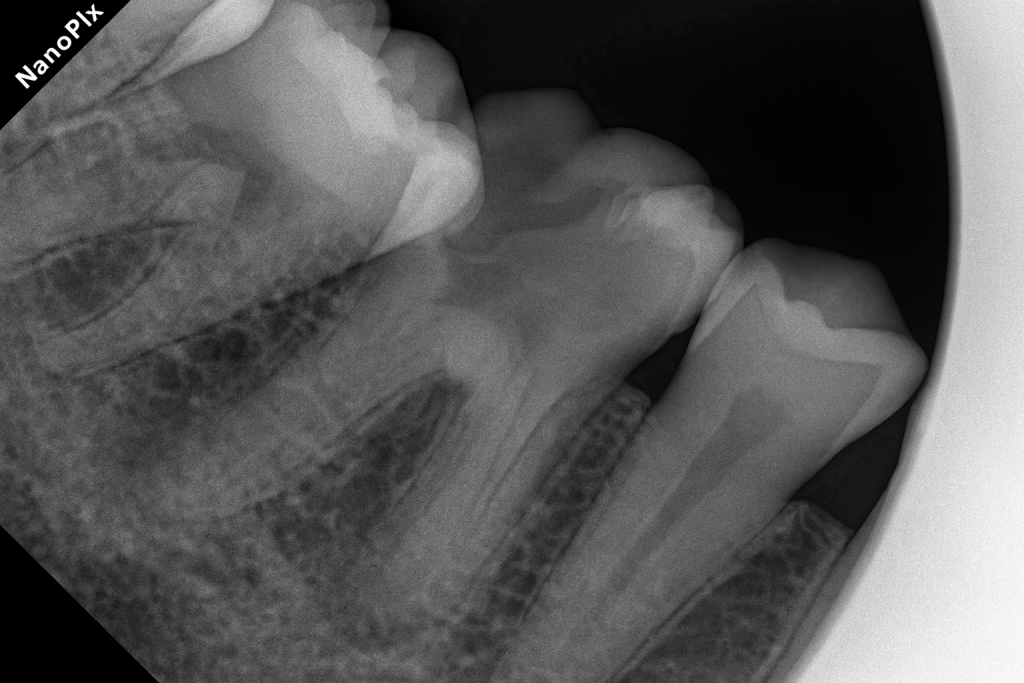

The patient presented with food lodgment and sensitivity over the lower right first molar. Radiograph revealed a deep Class II distal lesion approaching the pulp (Fig 1). Diagnosis: symptomatic irreversible pulpitis.

- Fig 1: Pre-op radiograph showing distal deep caries.